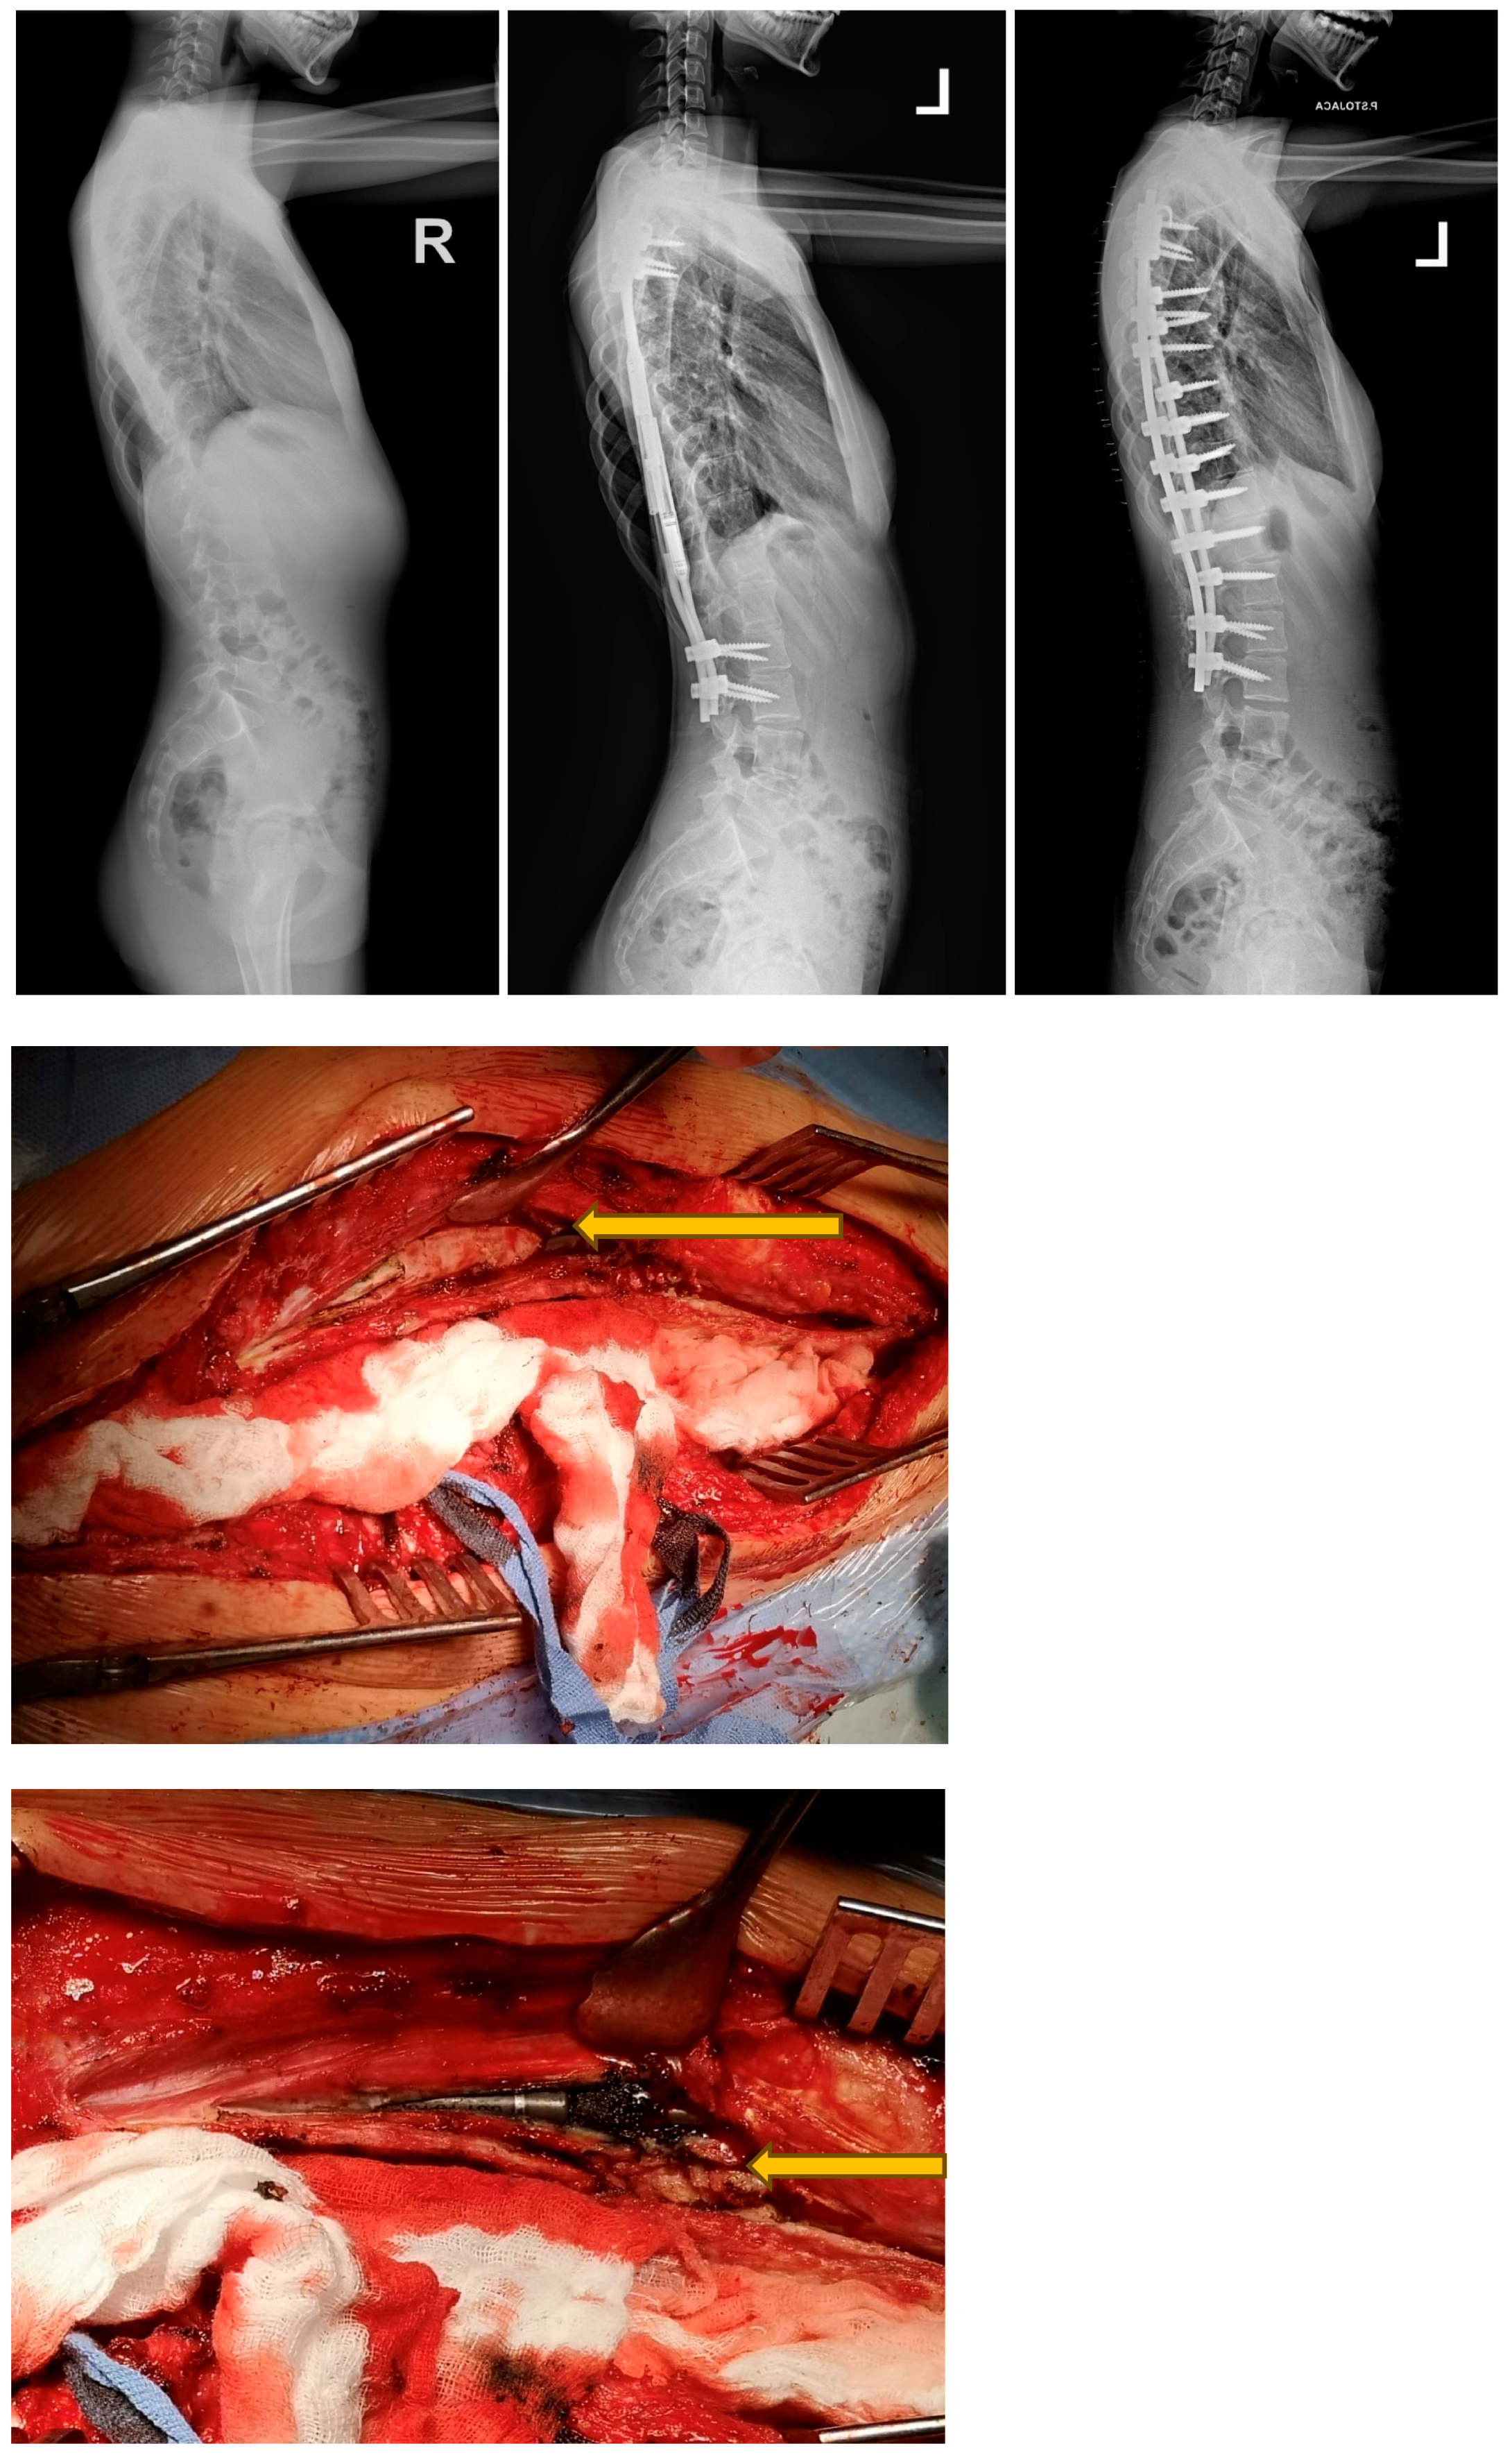

- Grabala, P.; Gupta, M.C.; Pereira, D.E.; Latalski, M.; Danielewicz, A.; Glowka, P.; Grabala, M. Radiological Outcomes of Magnetically Controlled Growing Rods for the Treatment of Children with Various Etiologies of Early-Onset Scoliosis—A Multicenter Study. J. Clin. Med. 2024, 13, 1529. [Google Scholar] [CrossRef] [PubMed]